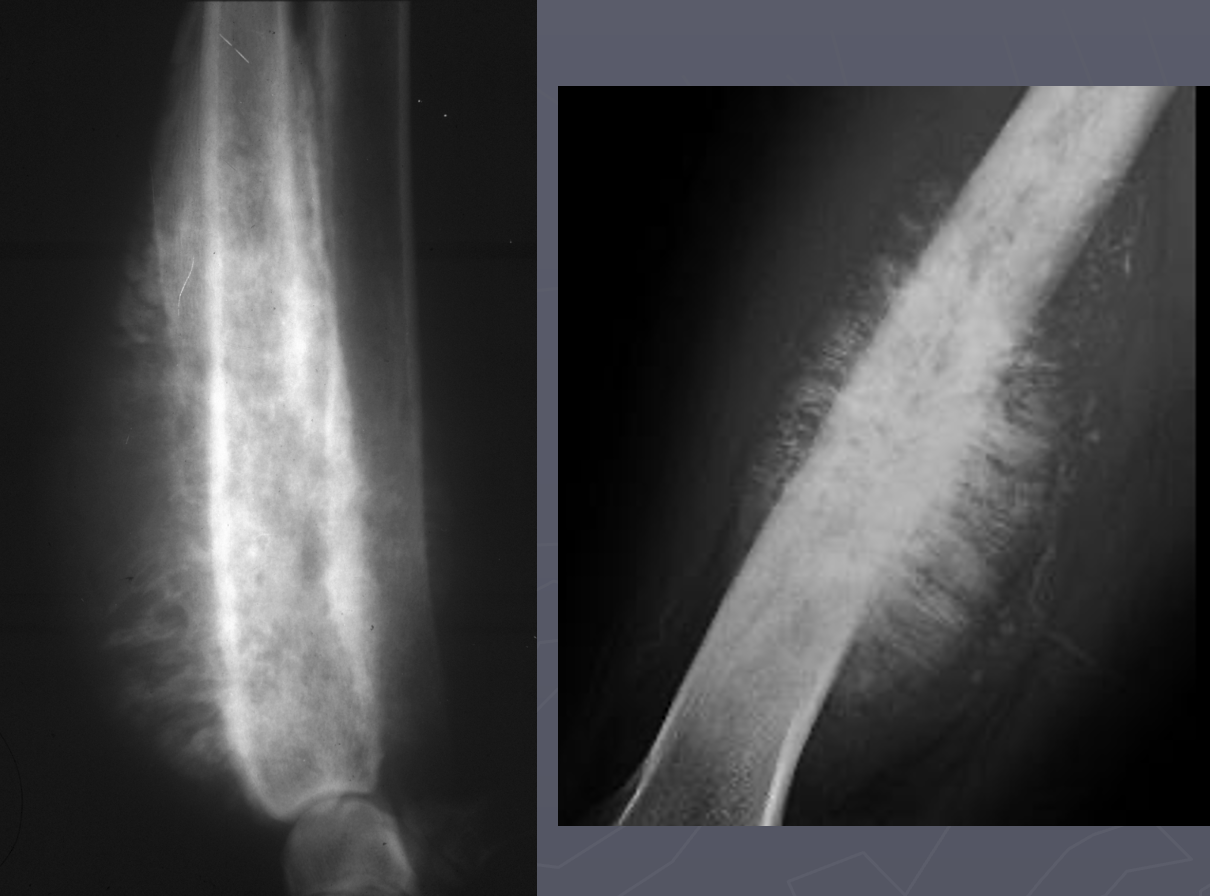

What is seen in these radiographs?

solid periosteal reaction